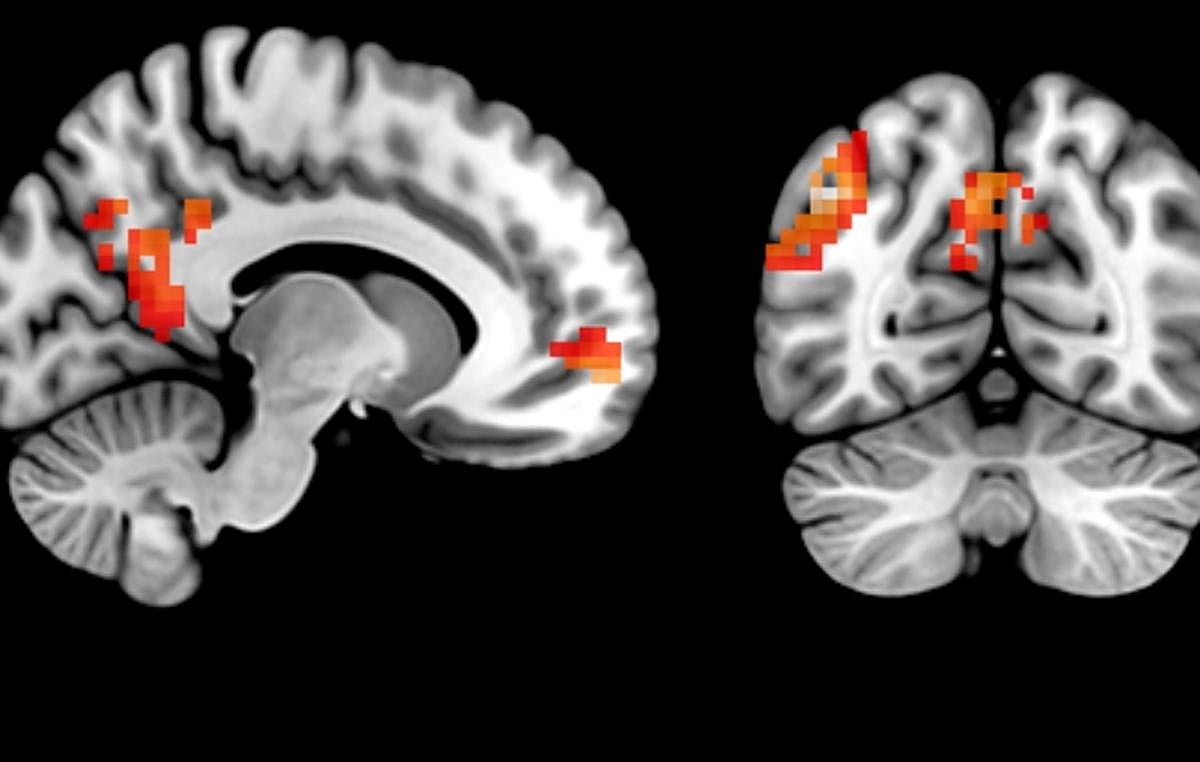

Los resultados señalan que los contenidos personalizados, en comparación con los que no lo son, provocan una mayor activación en redes cerebrales asociadas con la selección selectiva y la comprensión del mensaje (es decir, en el hipocampo anterior y posterior). Además, durante la fase de recuerdo libre, los participantes del estudio muestran una activación más intensa en áreas cerebrales implicadas en la recuperación de la memoria ante los mensajes personalizados (como el precúneo, el giro angular, la corteza prefrontal ventromedial y el hipocampo).

Concretamente, los investigadores han reclutado a personas con hábitos alimentarios poco saludables y han analizado su actividad cerebral mientras permanecían dentro de un escáner. Durante el experimento, los participantes han realizado dos tareas: primero, leer mensajes personalizados —adaptados a sus características concretas— y mensajes genéricos; después, se les ha pedido que recuerden e imaginen libremente el contenido de esos mensajes mientras se escaneaba su cerebro. Esto ha permitido a los investigadores observar cómo cada tipo de mensaje se procesa y almacena en el cerebro.